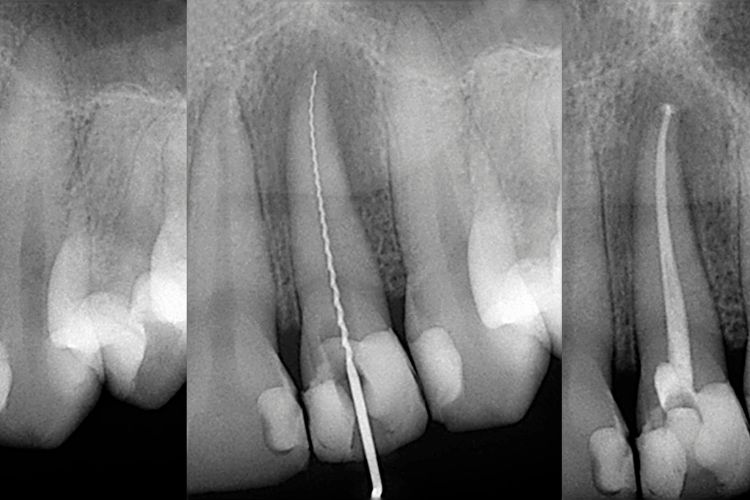

La endodoncia es un procedimiento odontológico que permite conservar un diente dañado o infectado, en lugar de extraerlo. Básicamente, consiste en retirar la pulpa dental (el tejido nervioso y vascular que está dentro del diente), limpiar la zona afectada y sellarla de manera segura para evitar que vuelva la infección.

Una vez realizada la endodoncia, el siguiente paso es restaurar el diente para que quede protegido y funcional. No todos los casos son iguales, y la elección dependerá del grado de destrucción de la pieza. Estas son las opciones más comunes:

Reconstrucción con poste de fibra de vidrio

Si el diente ha perdido mucha estructura, se coloca un poste dentro del conducto tratado. Este refuerza el diente y sirve de soporte para la reconstrucción. Es una opción muy utilizada por su resistencia y estética.